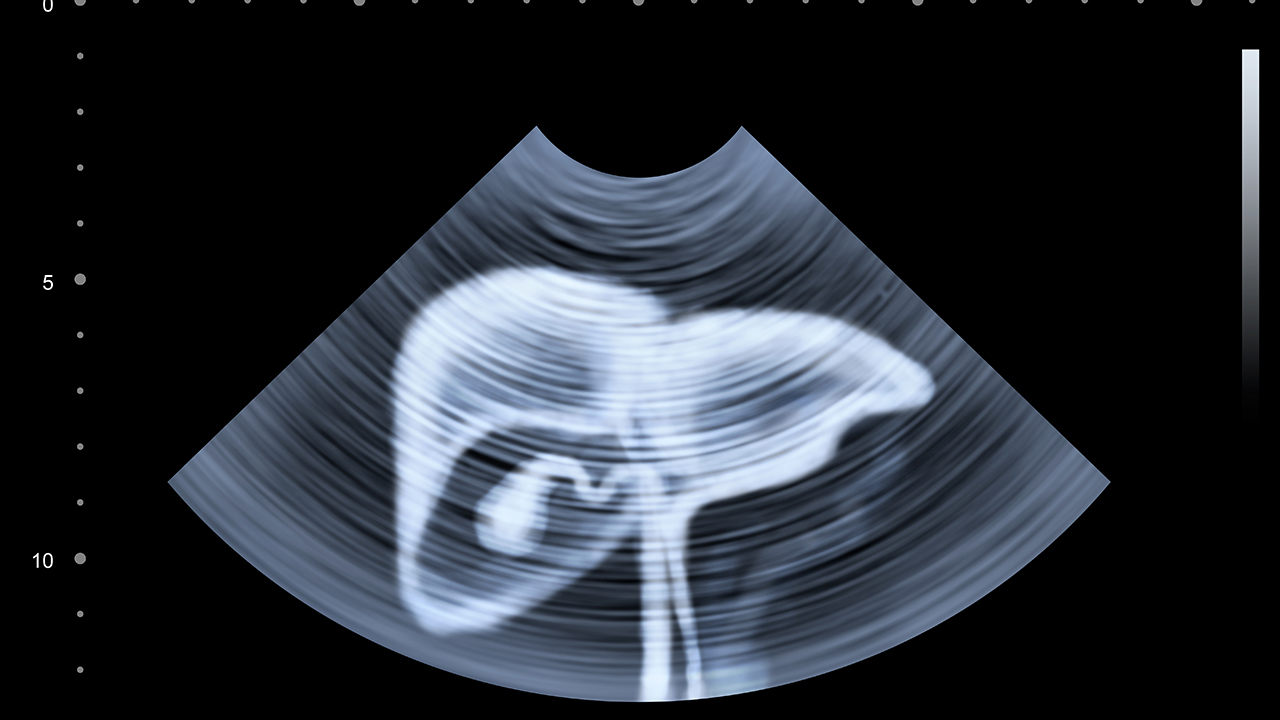

中南大學(xué)湘雅醫(yī)院是湖南省乃至全國(guó)知名的綜合性三甲醫(yī)院,其肝膽外科和腫瘤科在肝癌治療方面具有顯著優(yōu)勢(shì)。醫(yī)院配備了的影像診斷設(shè)備和手術(shù)設(shè)施,能夠開展肝癌的早期篩查、診斷以及復(fù)雜手術(shù)。醫(yī)院還參與多項(xiàng)肝癌治療的臨床研究,為患者提供新的治療方案。此外,醫(yī)院的多學(xué)科協(xié)作模式確保了肝癌患者的綜合治療和個(gè)性化護(hù)理。

湖南省腫瘤醫(yī)院是湖南省內(nèi)專注于腫瘤治療的機(jī)構(gòu),肝癌治療是其重點(diǎn)學(xué)科之一。醫(yī)院擁有現(xiàn)代化的放療設(shè)備和介入治療技術(shù),能夠?yàn)楦伟┗颊咛峁┦中g(shù)、放療、化療、靶向治療等多種治療手段。醫(yī)院的肝癌診療團(tuán)隊(duì)經(jīng)驗(yàn)豐富,尤其在晚期肝癌的綜合治療方面具有較高的成功率。醫(yī)院還注重患者的心理支持和康復(fù)指導(dǎo),幫助患者提高生活質(zhì)量。

中南大學(xué)湘雅二醫(yī)院在肝癌治療領(lǐng)域同樣具有較高的聲譽(yù),其肝膽胰外科和腫瘤中心在肝癌的微創(chuàng)手術(shù)和綜合治療方面表現(xiàn)突出。醫(yī)院引進(jìn)了國(guó)際的肝腫瘤消融技術(shù)和介入治療設(shè)備,能夠?yàn)榛颊咛峁⑽?chuàng)的治療方案。醫(yī)院還注重肝癌的預(yù)防和早期篩查,通過(guò)健康教育和社區(qū)合作,提高公眾對(duì)肝癌的認(rèn)識(shí)和防范意識(shí)。